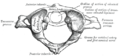

寰椎(C1)和枢椎(C2)是最起始的两个椎骨。

寰椎C1,是最起始的脊椎骨,与枢椎一起构成连接头颅与脊柱的关节连接。它的主要特点是它没有椎体,因为寰椎的椎体与枢椎椎体相融合。

• 第一颈椎,或寰椎。